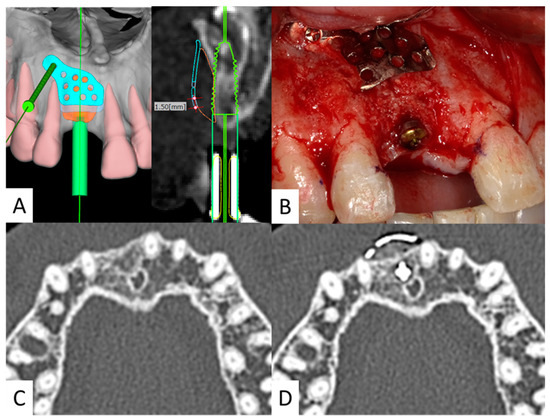

2.2. Fabricate SLM Titanium Mesh

2.4. Case Presentation